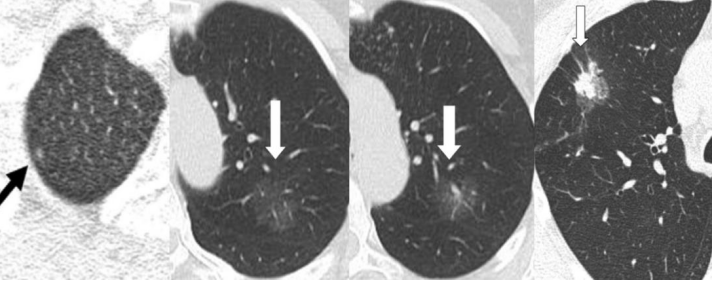

并不是所有的GGO都是肺癌的表现。但是有以下几点表现的GGO应当警惕肺癌,需要及时找专业的胸外科医生就诊。

1、非弥漫性GGO病灶直径大于8mm。病灶直径越大其为恶性的可能性也越大,当直径大于8mm时恶性明显多于良性。

2、内部成分。含有实性组织成分的病灶恶性可能性更高,实性成分越多恶性可能性越大。如上文介绍的“荷包蛋状”GGO

3、病灶形态。空泡型GGO、有分叶或毛刺、胸膜凹陷、血管集束及支气管充气等征象时恶性可能性大。

4、在定期复查中,发现病灶逐渐增大、颜色变实、实性成分增多(影像学表现为密度增加)要高度怀疑肺癌。

图五 恶性病灶影像学表现

图六 由左到右依次为非典型腺瘤样增生,原位腺癌,微浸润癌,贴壁生长为主的腺癌。